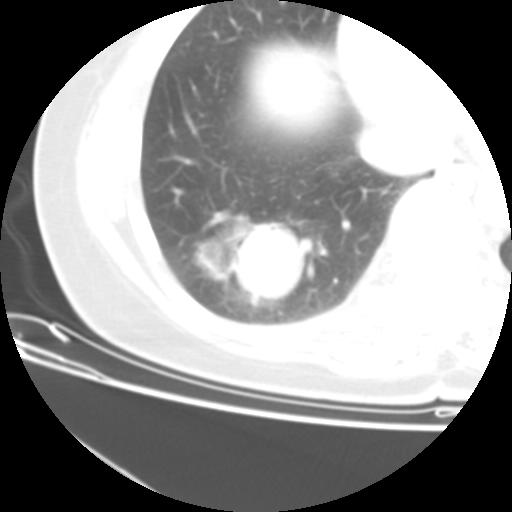

女 46岁,咳嗽咳血10月

【linyiming】右肺下叶见类圆形软组织影,边缘欠规整,略分叶状。考虑炎症假瘤可能?

未排除周围型肺癌。建议CT增强。

【aosangwa】肺癌的主要特征是:毛刺征、分叶征及胸膜凹陷征,此病例位于右肺下叶距胸膜很近,但没有胸膜凹陷征,其周围像示渗出性病变,病灶在两窗上没有大小没有发生大小改变。

考虑其良性肿瘤,炎性假瘤可能性大,其主要鉴别是:结核球、周围型肺癌、血管瘤

病理诊断类癌(周围型)。